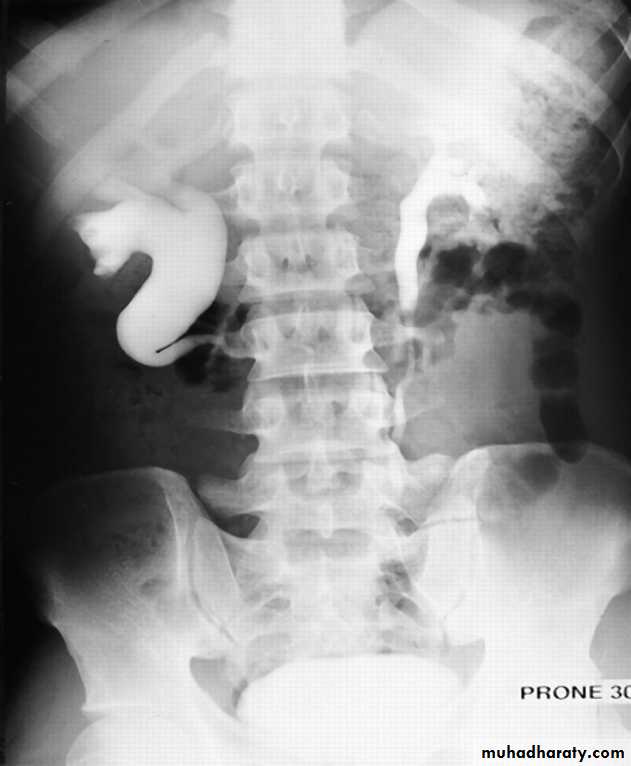

IVU shows

1. The kidneys at low position .

2.Close to the spine with long axis parallel to the spine .

3. Malrotation manifested by medially directed calyces.

4- The renal pelvis and ureters are anterior and lateral in position .